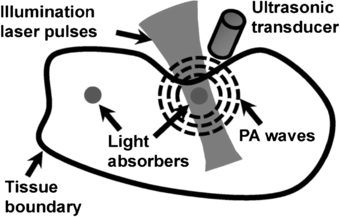

3.3. Photoacoustic tomography

Photoacoustic (or optoacoustic) tomography (PT) is an umbrella term for a range of imaging methods that can provide detailed images of tissue types and blood oxygenation levels. PT can image blood vessels in highly scattering tissue and can discriminate between arteries and veins (Kruger et al 1995). An excellent review of the technology is given by Beard (2011).

PT combines optical absorption contrast and highly scalable spatial resolution i.e. from micrometer optical resolution to millimetre acoustic resolution. PT has three main embodiments: microscopy, computed tomography, and endoscopy (Hu and Wang 2010a, 2010b) with representative applications in microvascular-related physiological and pathophysiological research, including haemodynamic monitoring, chronic imaging, tumour–vascular interaction (Ehling et al 2013), neurovascular coupling (Hu and Wang 2010a), and drug discovery biomarkers (Bednar and Ntziachristos 2012).

3.3.1. Background

PT involves shining a very short light pulse (typically a few tens of ns width) onto tissue via an optical fibre. Wherever this light is absorbed, the energy from the light warms that region of tissue or blood, in the region of one thousandth of a degree Kelvin. This warming causes the absorbing region to expand rapidly by a very small amount, with this thermoelastic expansion causing a pressure wave to be set up which travels through the tissue at the speed of sound, before being picked up by a high frequency (e.g. 30–70 MHz) focussed ultrasound detector. The more a section of tissue or region of blood absorbs, the hotter it becomes and the greater the ultrasound signal it creates. So unlike a standard ultrasound image, the photoacoustic image reveals the different optical absorption properties of tissue or blood (figure 23). As with diffuse optical tomography different wavelengths of light, for example green and infrared, are used to reveal varying levels of oxygenation in the blood as well as different tissue types (extract from 'IPEM Spotlight on Optical techniques in Medical Imaging', 2006).

Figure 23. Photoacoustic tomography imaging method (permission granted to re-use from Yao and Wang 2011 Contrast Media Mol. Imaging 6 332–45). Photoacoustic signals are induced by pulsed laser illumination. When laser energy is absorbed by biological tissues, the resulting very minimal heating of the tissues generates ultrasonic waves. The waves can be detected by a transducer and then used to create an image of the optical absorption distribution inside the tissues. Different soft tissue types in the body differentially absorb laser light of different wavelengths, providing high inherent contrast.

Download figure:

Standard image High-resolution imageThe technique can provide 3D images with significant depth of penetration up to 7 cm. The image resolution is in the order of 10–100 µm. Image acquisition time can be of the order of tens of minutes. PT imaging has the important advantage that the photoacoustic signals can be detected on the same side and over the same region of tissue that is irradiated with the excitation light (figure 24). This is particularly important for imaging skin and superficial blood vessels (figure 25).

Figure 24. Spatial resolution versus penetration depth in multi-scale PT (summary reproduced with permission from Hu and Wang 2010a Front. Neuroenerg. 2 10). SM-PAM: sub-micron photoacoustic microscopy; OR-PAM: optical-resolution photoacoustic microscopy; AR-PAM: acoustic-resolution photoacoustic microscopy; OD-PACT: optical-detection-based photoacoustic computed tomography; AR-PAMac: acoustic-resolution photoacoustic macroscopy; C-PACT: circular photoacoustic computed tomography.

Download figure:

Standard image High-resolution imageFigure 25. Photoacoustic tomography (PT) example images of mouse model microvasculature from head measurements (permission granted to re-use from Hu and Wang 2010b J. Biomed. Opt. 15 011101), giving time resolved ultrasonic detection of (a) maximum amplitude projection image and (b) 3D morphology.